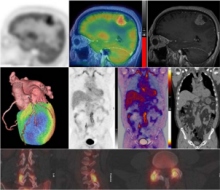

Clinical Nuclear Medicine PET-CT and PET-MRI

Curso de postgrado diseñado para profesionales de la salud involucrados en la práctica de la medicina nuclear e imagen molecular incluyendo especialistas en medicina nuclear, radiólogos, físicos médicos, residentes, estudiantes de medicina y tecnólogos.

El objetivo del curso es proporcionar el desarrollo profesional hasta la fecha a través de la revisión de las aplicaciones clínicas establecidas y emergentes de la medicina nuclear y diagnóstico por imagen molecular.